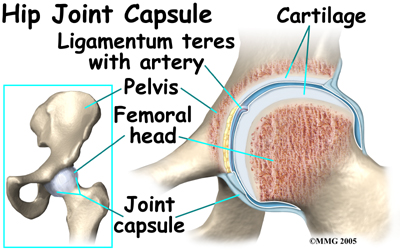

The hip joint is where the thighbone (femur) connects to the pelvis. The joint is made up of two parts. The upper end of the femur is shaped like a ball. It is called the femoral head. The femoral head fits into a socket in the pelvis called the acetabulum. This ball and socket joint is what allows us to move our leg in many directions in relation to our body.

In the growing child, there are special structures at the end of most bones called growth plates. The growth plate is sandwiched between two special areas of the bone called the epiphysis and the metaphysis. The growth plate is made of a special type of cartilage that builds bone on top of the end of the metaphysis and lengthens the bone as we grow. In the hip joint, the femoral head is one of the epiphyses of the femur.

The capital femoral epiphysis is somewhat unique. It is one of the few epiphyses in the body that is inside the joint capsule. (The joint capsule is the tissue that surrounds the joint.) The blood vessels that go to the epiphysis run along the side of the femoral neck and are in danger of being torn or pinched off if something happens to the growth plate. This can result in a loss of the blood supply to the epiphysis.